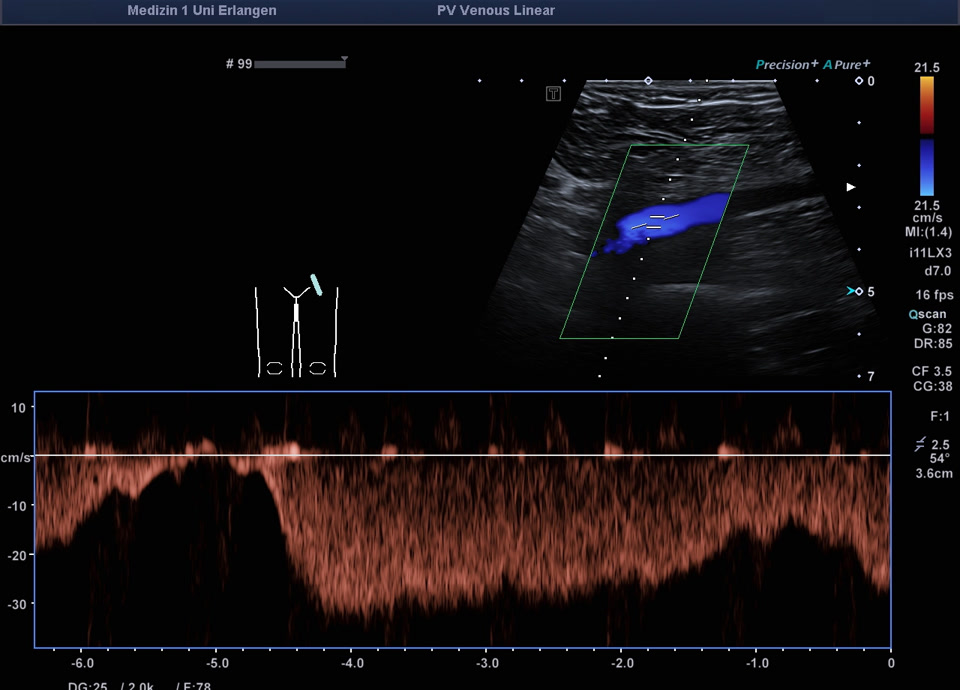

Normalbefunde

• Regelrechtes Flussprofil V. iliaca externa (PW-Dopplervideo)

• Flussprofil V. iliaca externa Valsalva-Manöver (PW-Doppler)

• Regelrechtes Flussprofil V. iliaca externa (Farbdopplervideo)